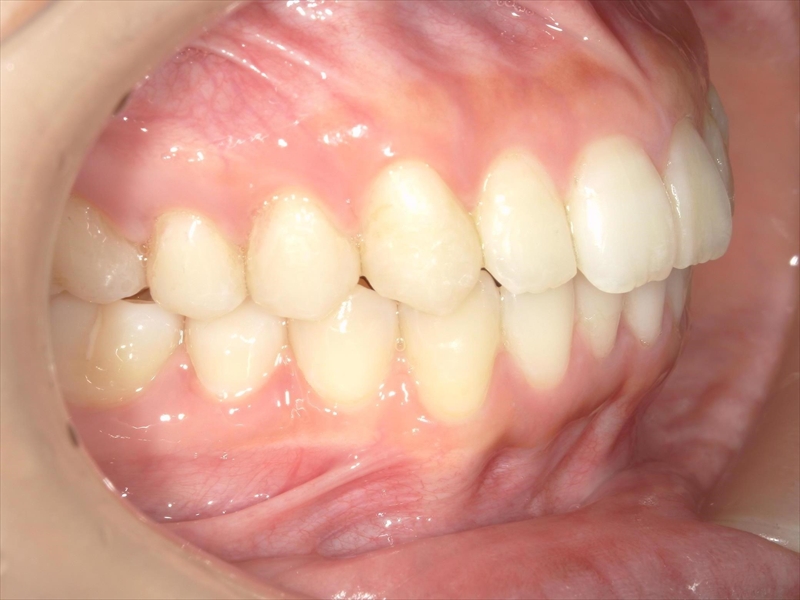

また、奥歯の噛み合わせにも問題があり、本来は半歯分ずつずれて噛み合うべきところが、正しく機能していない状態でした。

- 上顎出っ歯が原因で下顎前歯が上に伸び過ぎているため、圧下

- 犬歯から小臼歯までが捻じれていたため、正しい位置へ

- 大臼歯は内側へ入れ

治療前後 写真